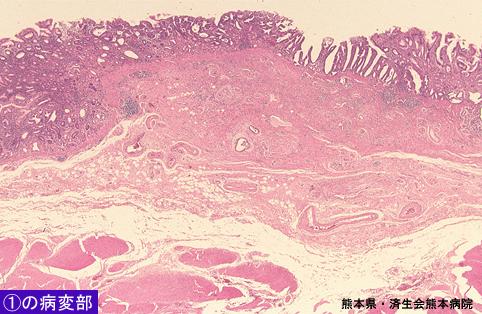

clasificación del pacienteTumor Epitelial Maligno/Adenocarcinoma

parte(separada por órganos)estómago(región)/cuerpo

método de exámenMicro

clasificación ectoscópica de tumoresTipo 0(tipo superficial)/Tipo IIc(IIc)

diámetro mayor del tumor1 - 9

grado de penetraciónsm